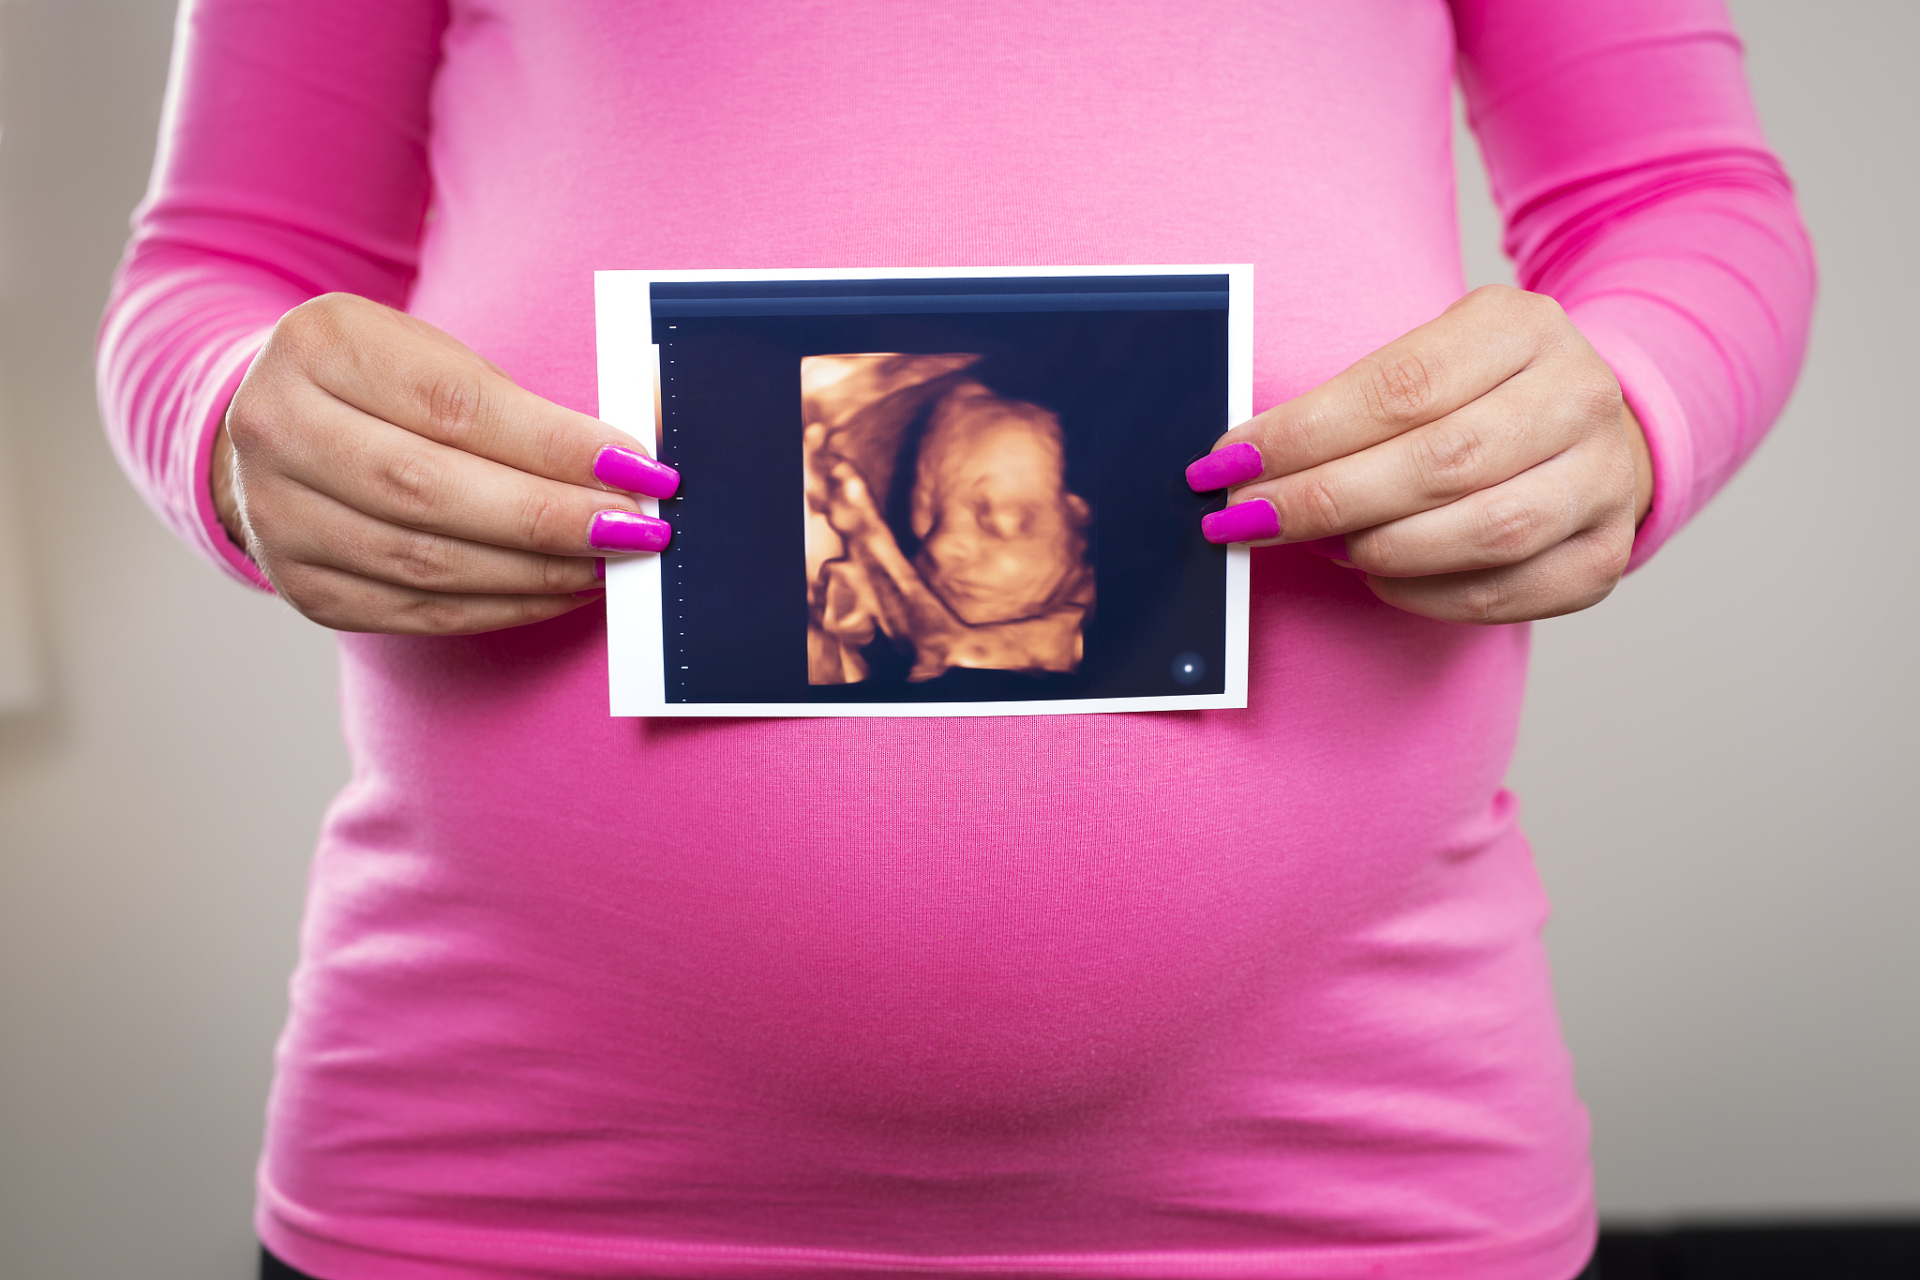

四维ac代表胎儿腹围,反映胎儿发育情况.